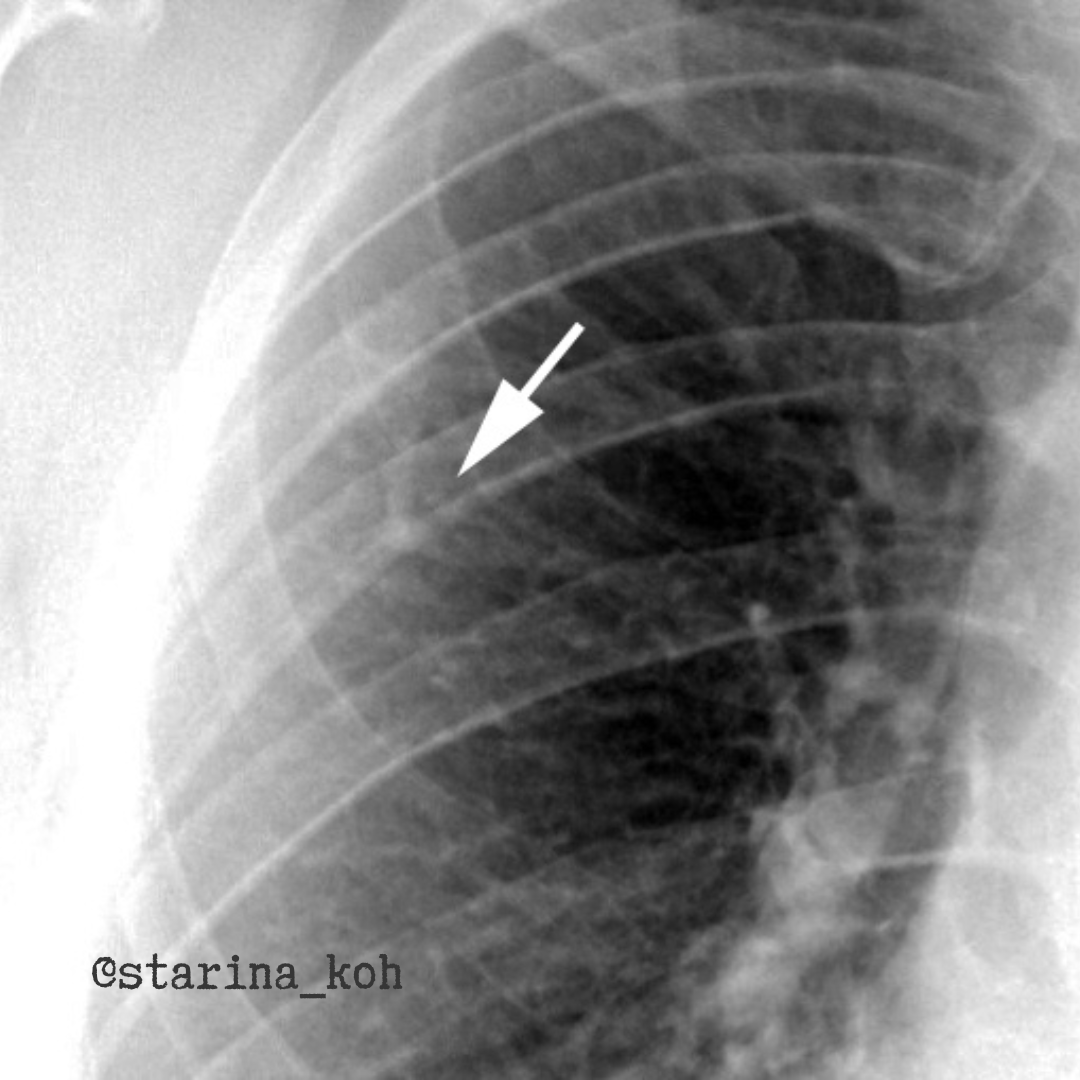

Нашу коллегу-терапевта, красивую молодую девушку ничто бы не беспокоило, если бы эти фтизиатры (хехе) не придумали свои профилактические осмотры с НДКТ, где в легких выявили не совсем типичные для туберкулеза очаги. На самом деле, подозрительный очаг можно выявить и на флюорографии - присмотритесь, он помечен стрелкой.

Так вот, после НДКТ у пациентки очаг был трактован как артериовенозная мальформация (АВМ). Можно встретить также название ангиомы или фистулы. Доказать подобную аномалию развития можно только при введении контрастного препарата и убедиться, что в легком есть своеобразные "клубочки", в которых отсутствует капиллярное русло, а кровь напрямую сбрасывается из системы легочной артерии в вены.

И мы сделали такое исследование - обнаружили, что такие "клубочки" активно заполняются контрастом уже в артериальную фазу. При внимательном рассмотрении исследовании мы выявили, что в легких присутствует далеко не одна такая АВМ - а нашли их целых 4 штуки - разной формы и размеров - с обеих сторон. При нативном исследовании в сторону АВМ можно подумать также проанализировав сосуды, подходящие к данному очагу в/д справа - он не соответствует нормальному калибру сосудов данной зоны.